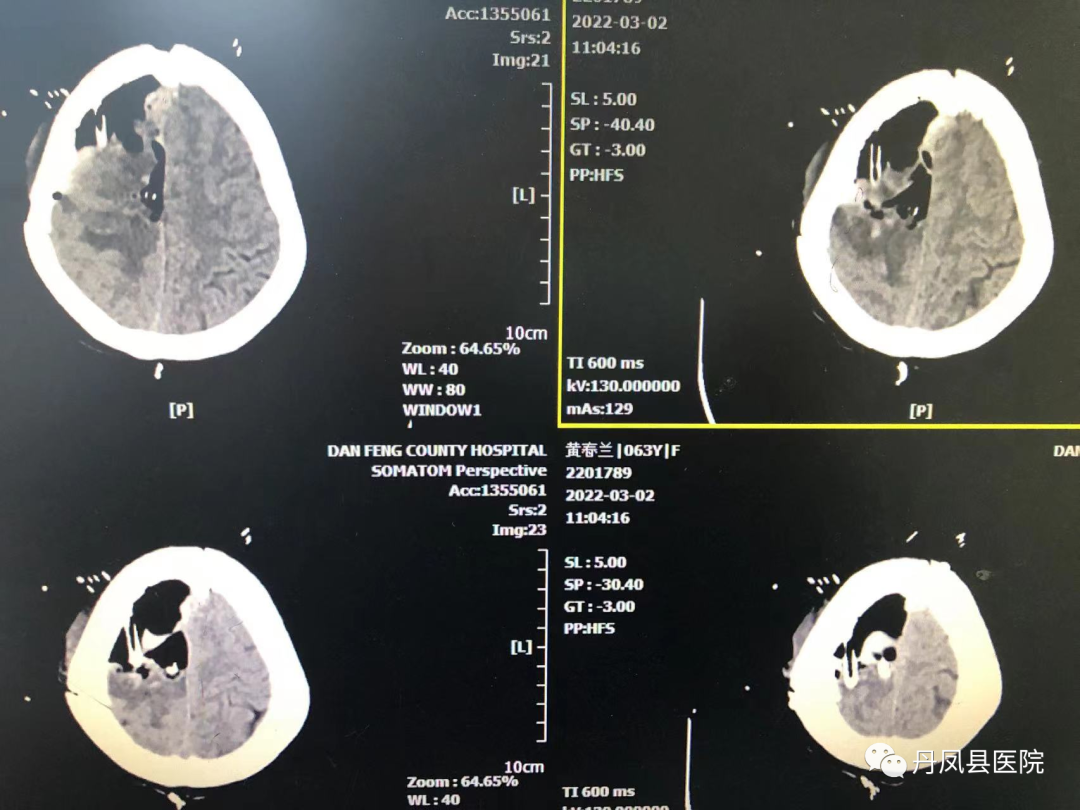

图为术中切除组织病检报告术后第二天,患者神志清楚,可以配合完成指令动作,复查CT显示:“颅内肿瘤全切”。目前,患者病情稳定,在肢体功能康复中。

![]()

术后复查CT显示:颅内肿瘤全切